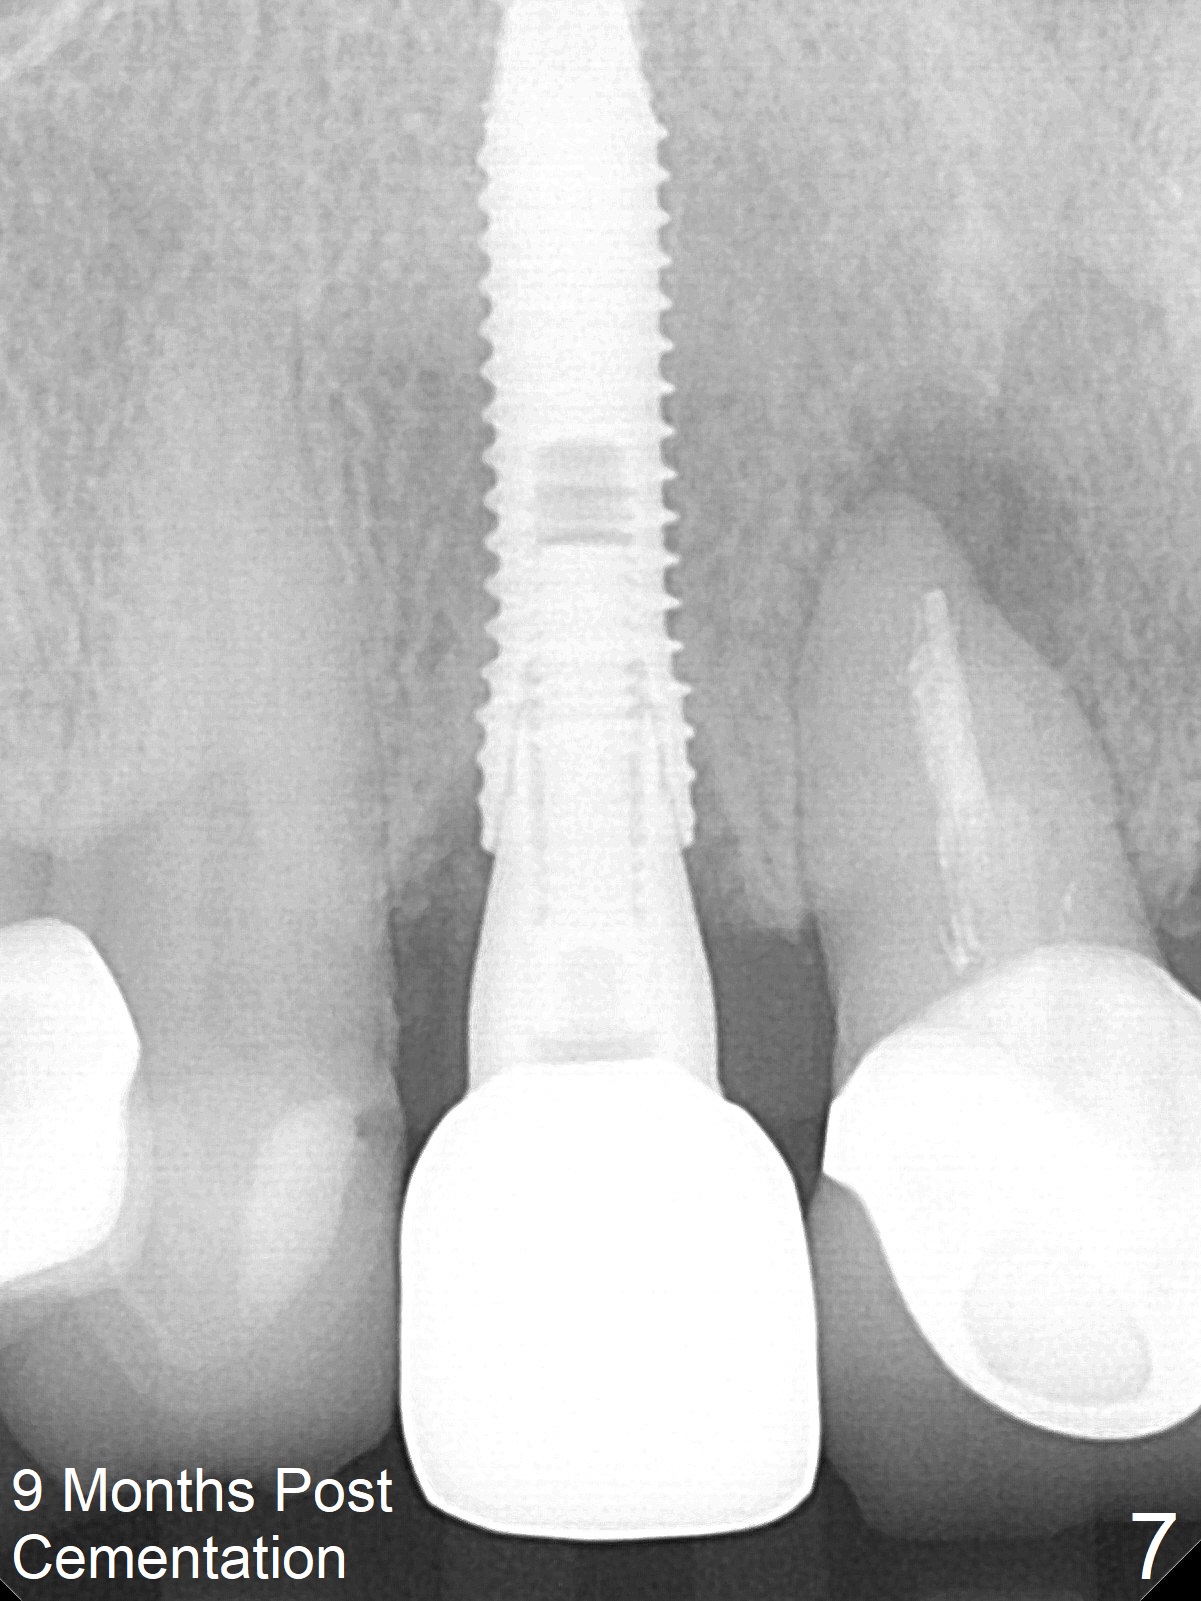

She returns for impression 4 months postop; the abutment margin is substantially subgingival (Fig.6 arrow). The abutment is changed to 4.5x4(4) mm one before impression. There is no bone resorption 9 months post cementation (Fig.7).